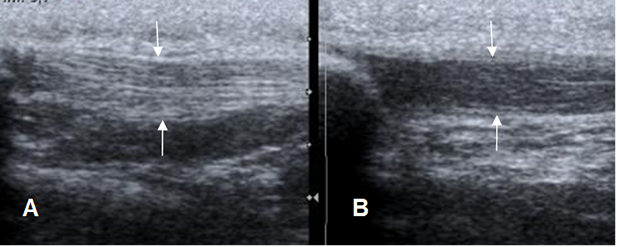

Fig 147. Tendinitis aguda del patelar.

A: Ecografía sagital. Tendón patelar de ecogenicidad normal.

B: Ecografía sagital. Tendón patelar hipoecoico y con pérdida de su patrón fibrilar, por inflamación aguda.